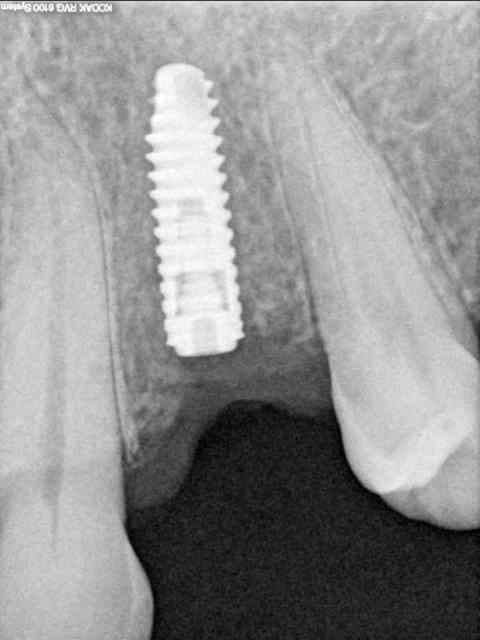

Si une vis de couverture operculise, peut-on vraiment espèrer que le niveau osseux sous-jacent soit toujours le même? Compromis avec l'espace biologique nous dirait béotien! Toujours est-il que si t'as déjà perdu 2 mm sur un implant de 8 mm avant la mise en charge, ça ne s'annonce pas super, non?

parce que pour toi operculisation=perte osseuse systématique?

désolé, mais j'ai "réouvert" mardi pour 2 implants (15 et 16), l'un operculisé et l'autre non...perte osseuse de celui operculisé (celui en 16) =0mm....(pour l'autre pareil)

ah oui, mais c'était un 5.7mm de diamètre...

Si t'as posé un 5.7 pour une 16, tu devais avoir une belle largeur de crête (certainement pas 6 ou 7 mm mais plutôt 9), non? Ton implant a suffisament d'os en vestibulaire et en palatin pour que cet os soit vascularisé et donc stable dans le temps. Donc pas de perte.

Quand tu pose un 3.8 en 16, tu cherches un compromis entre un implant assez large pour soutenir ta molaire et un implant pas trop large pour qu'il soit quand même entouré d'os. Résultat pas assez d'os (généralement en vestibulaire pour que ton implant soit quand même à peu près en bonne occlusion), donc pas de vascularisation, donc perte osseuse.

Je ne pense pas que cela soit comparable.

dis moi la tu le trouves comment mon compromis avec l'espace biologique

eii

d'après toi faites il y a combien de temps?

Superbe ratrapage suite à une operculisation d'une vis de couverture. Félicitations. Je te savais costaud béotien mais là tu m'impressionnes vraiment.

Je dirais fait il y a 11 ans 1/2? Alors.

- pas de vis de couverture , pas d'operculisation!!

Même pas de lambeau pédiculé palatin!